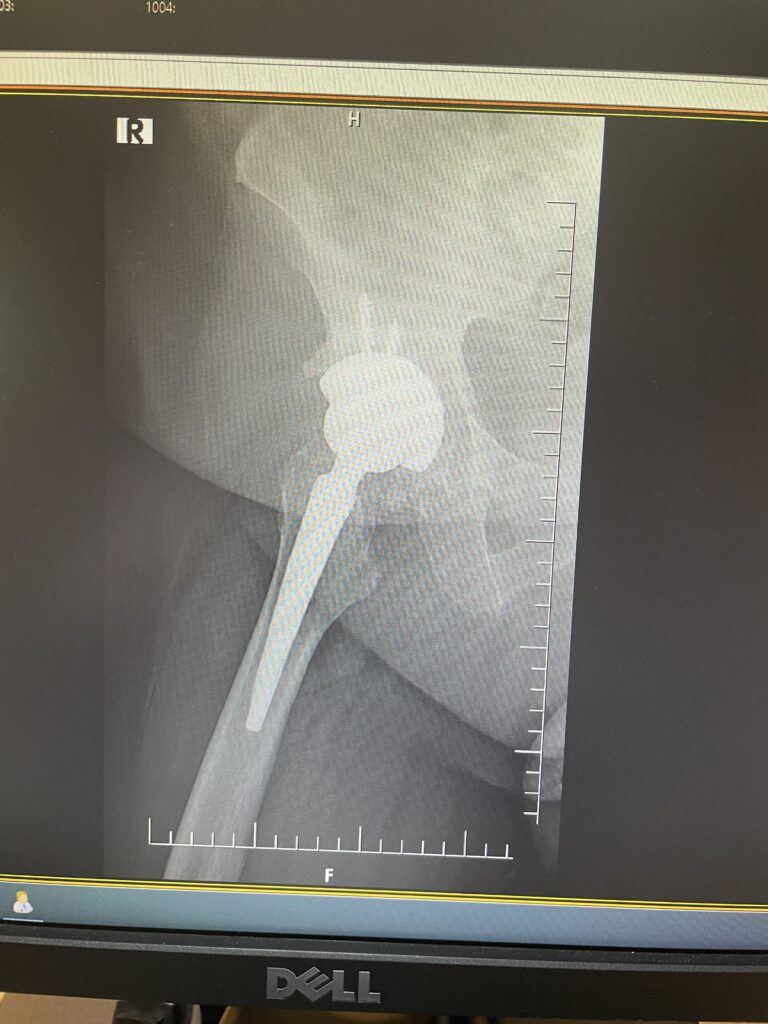

F.S.